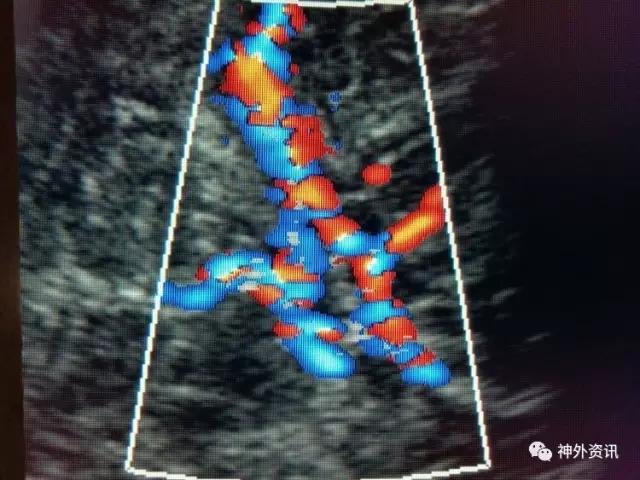

脑血流良好:

2017.2.4:术后5天复查颅脑CT,结果示中线居中,左侧半球及环池显示清晰,右侧半球脑沟显示欠清晰,脑组织低密度较前有所好转,继续同前治疗。已加用预消化肠内营养液及促进胃肠动力药物。